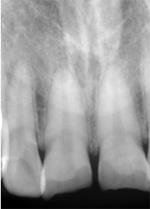

治療前のX線写真 |